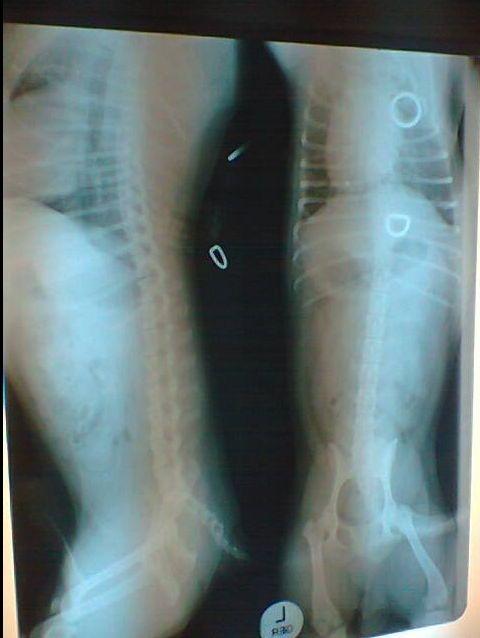

Sinds maandag heeft hij een hele harde buik. Het buikje is niet opgezet, alleen heel hard. Ook rilt hij heel erg veel alsof hij heel zenuwachtig is, of alsof hij het heel koud heeft.

Ik hoef er natuurlijk niet bij te vermelden dat Fawkes al lang bij de dierenarts is geweest. Maar tot nu toe heeft hij niets kunnen vinden. Hij heeft medicijnen gehad, maar deze doen nog niet. Er is een foto gemaakt, maar daar was niets op te zien, behalve een iets vergroot hart, maar dat komt vaker voor (volgens de DA)

Die ringetjes op de röntgenfoto zijn van het tuigje dat Fawkes om had op het moment van de foto.